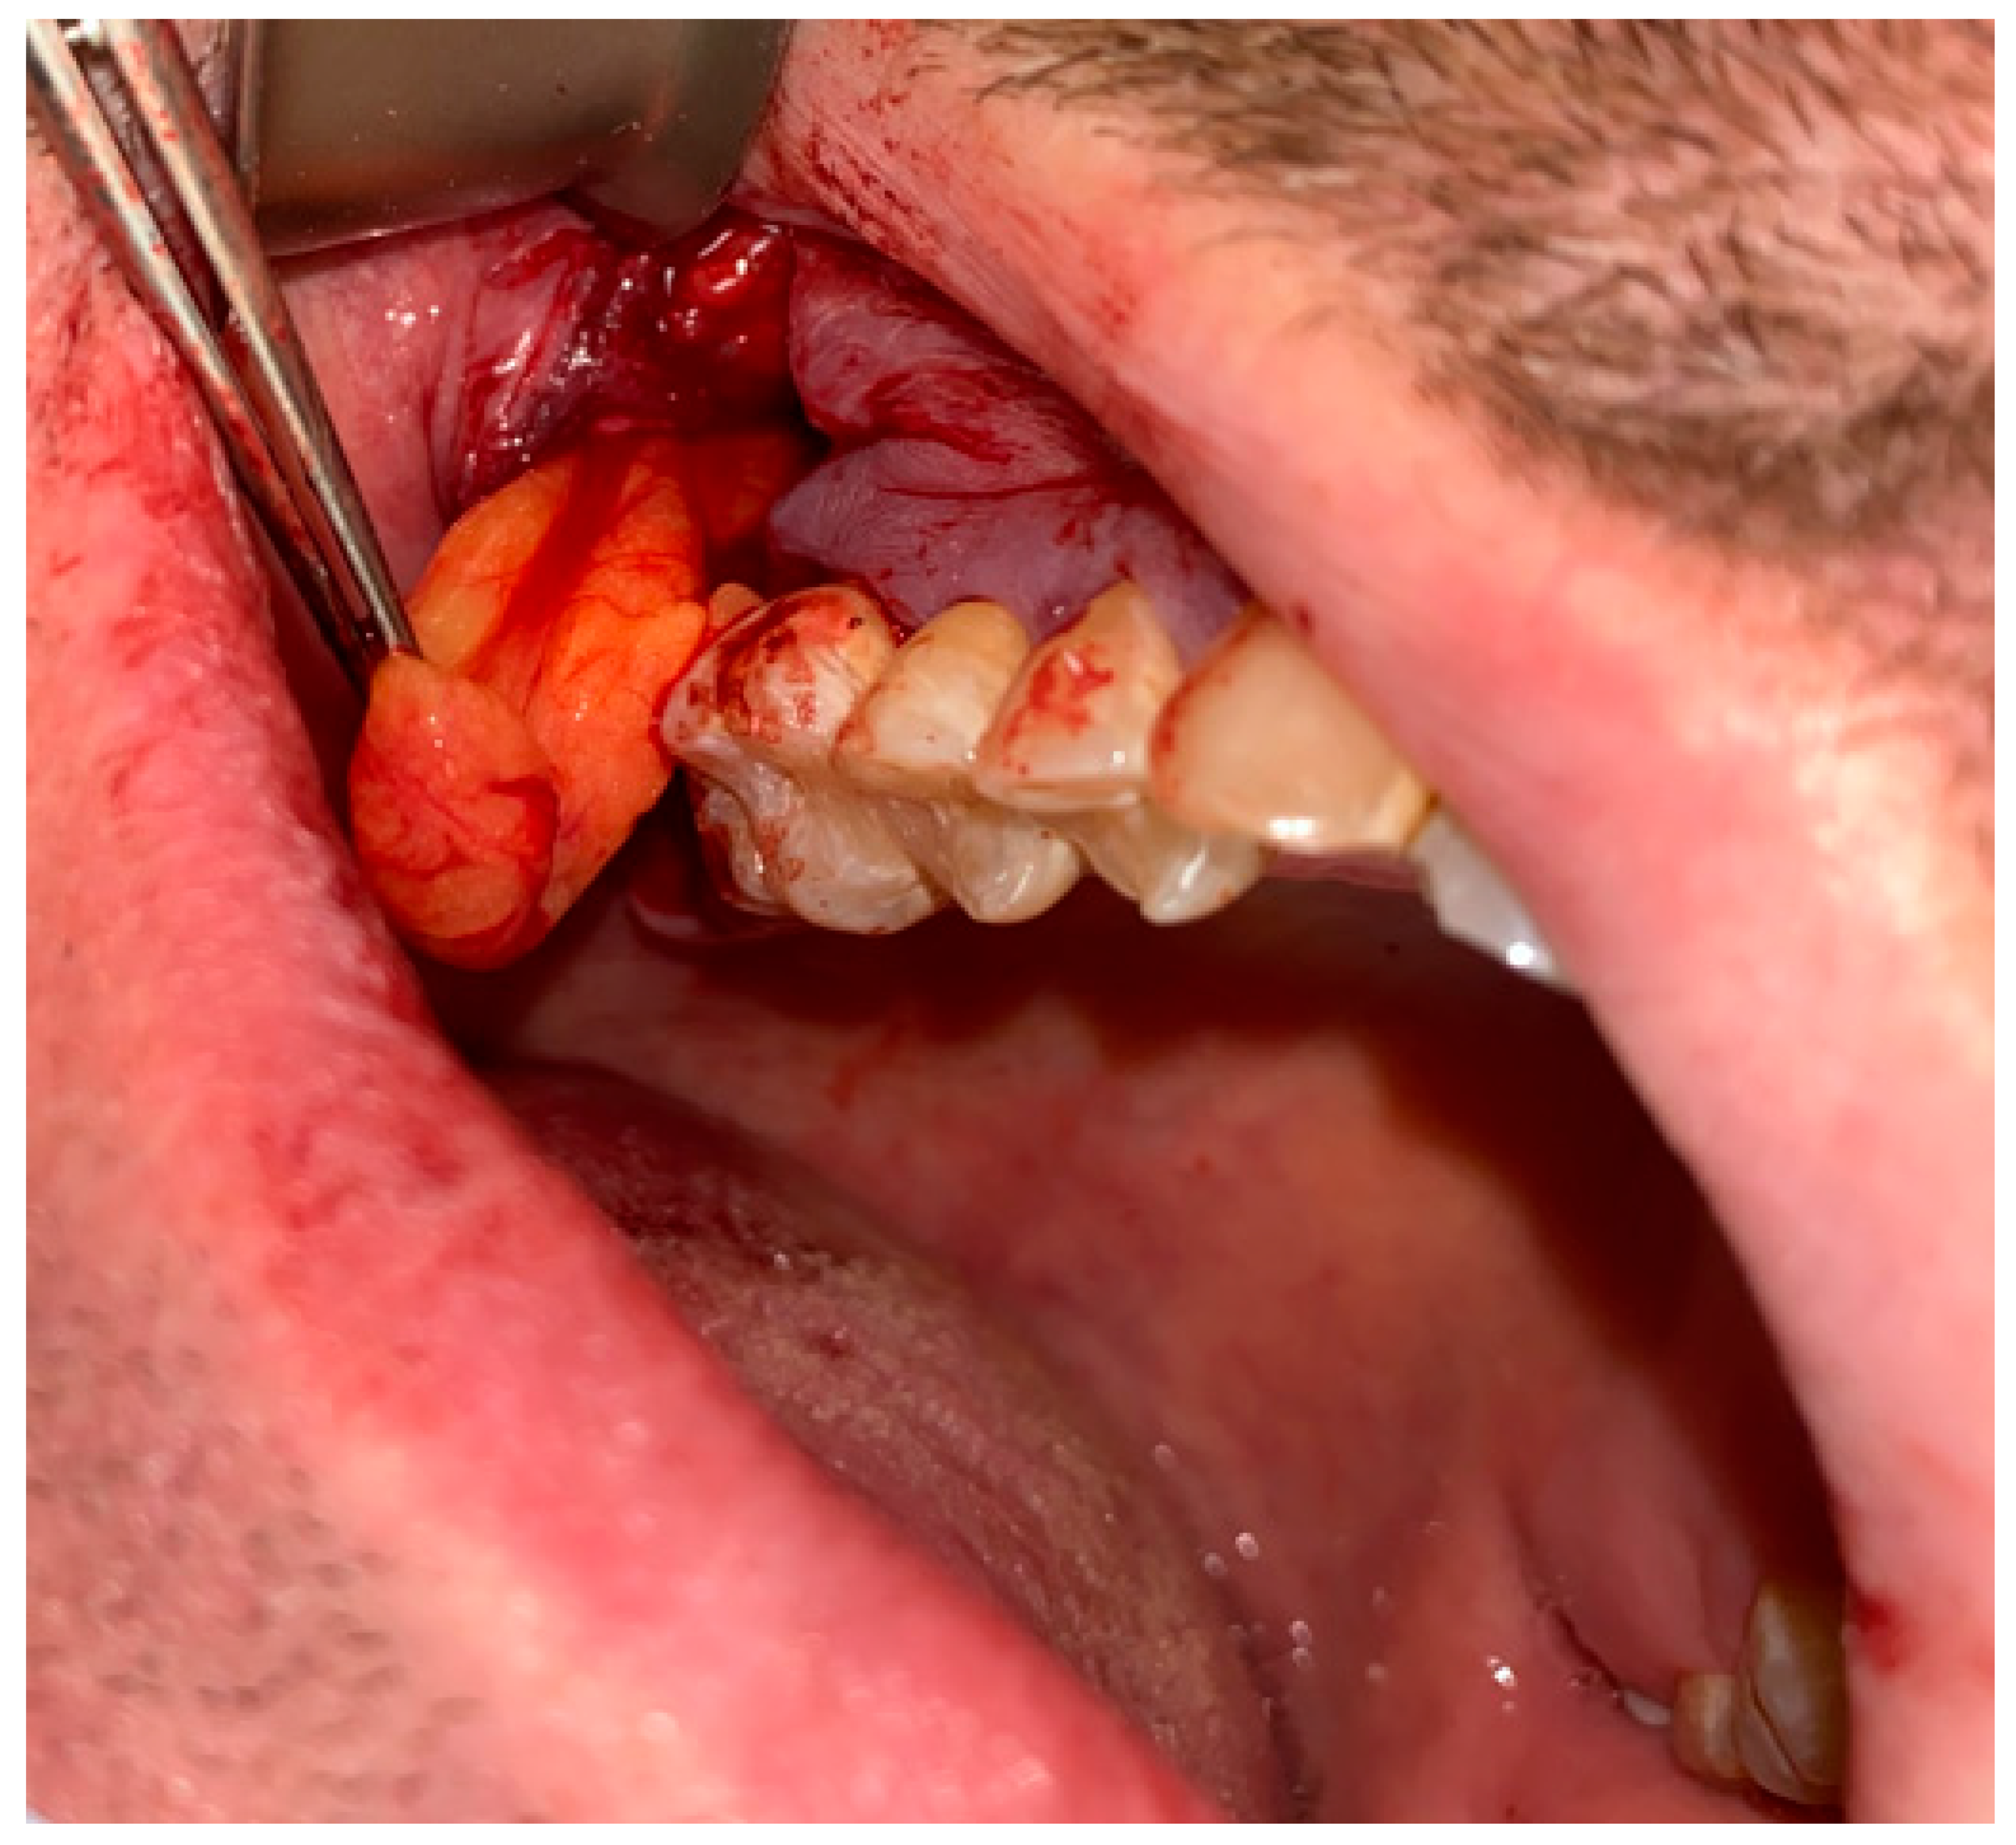

Figure 3. The bone defect was covered with the Bichat fat pad after mobilization. The entire defect will be sutured with vertical mattress sutures to the palate to ensure its proper position.

Figure 4. A very good result with limited buccal corridor narrowing and good tissue volume at the top of the dental arch.